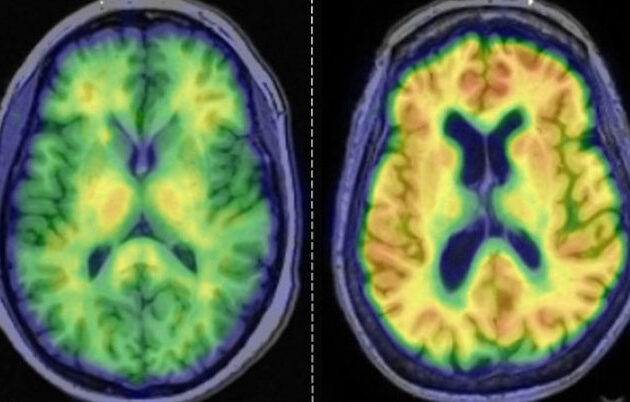

Reeder’s research, program leadership and entrepreneurship focus on the assessment and imaging of liver disease. His group develops innovative noninvasive imaging methods that improve the diagnosis and care of patients with liver disease and other abdominal illnesses.

As director of the UW Liver Imaging Research Program, he leads work on the technical development and translation of new liver imaging methods, particularly quantitative imaging biomarkers. Such biomarkers provide objective assessment of normal and pathogenic processes to aid in the detection, diagnosis and response to treatment. Reeder is also a founder of Calimetrix, a Madison-based startup that designs, manufactures and markets advanced MRI test objects called “phantoms” that aid in research.